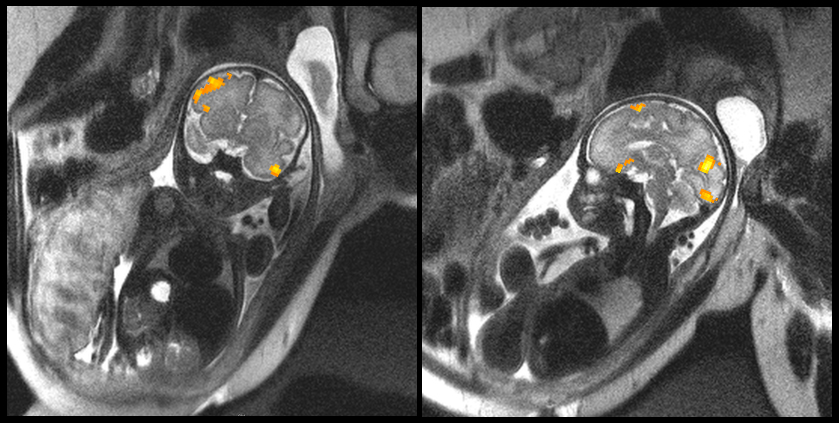

Los investigadores encontraron una diferencia en cómo ciertas regiones cerebrales se comunican entre sí en bebés prematuros. Aunque los resultados son preliminares debido a que el estudio era pequeño, se realizaron resonancia magnética funcional (fMRI) en 32 bebés (14 de ellos fueron prematuros), han podido comprobar la importancia del trabajo de la neuroimagen fetal. "Aprovechar el poder de estas herramientas avanzadas nos está ofreciendo por primera vez la oportunidad de explorar el inicio de los problemas neurológicos que están ocurren en el útero", dice Catherine Limperopoulos, una neurocientífico pediátrico en el Children's National Medical Center en Washington, D.C.

El equipo estudió la "conectividad funcional" en el cerebro, usando fMRI para determinar qué regiones cerebrales sincronizan la actividad cuando el sujeto no está involucrado en ninguna tarea en particular como es el caso del vientre materno. La actividad sincronizada entre las regiones del cerebro, según el pensamiento, muestra que esas regiones están bien conectadas y comparten información.

Uno de los principales hallazgos del estudio es que en el caso de los bebés prematuros se encontró un pequeño parche en el lado izquierdo del cerebro, en un área que se convierte en un centro de procesamiento del lenguaje, tenía una conectividad más débil con otras regiones del cerebro que en los bebés nacidos a término. Hao Huang, que estudia el desarrollo del cerebro neonatal en la Universidad de Pensilvania, considera "que detectar esta diferencia en la conectividad tan temprano es algo interesante". La detección temprana para problemas del lenguaje es la clave del éxito, por eso este estudio plantea la importancia de rastrear a estos niños nacidos prematuramente para poder ayudarles.

Este tipo de estudio habría sido imposible hace poco tiempo. Uno de los mayores problemas en la neuroimagen fetal es que un bebé dentro del saco amniótico es un objetivo en movimiento y difícil de realizar una resonancia magnética, pero gracias a las mejoras de los algoritmos Veronika Schöpf, matemática de la Universidad de Graz en Austria, han logrado captar con nitidez las resonancias en movimiento.